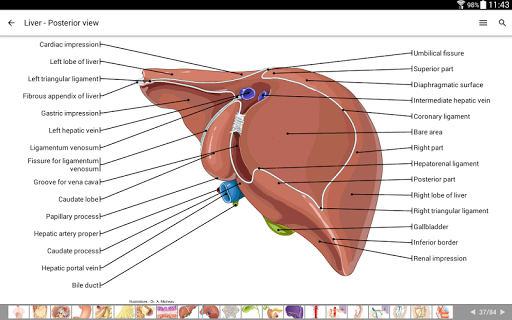

IMAIOS e-Anatomy adalah atlas anatomi manusia untuk dokter, ahli radiologi, mahasiswa kedokteran, dan teknisi radiologi. Dapatkan cuplikan lebih dari 26.000 gambar medis dan anatomi secara gratis sebelum berlangganan atlas anatomi manusia terperinci kami.

e-Anatomy didasarkan pada atlas daring IMAIOS e-Anatomy yang telah memenangkan penghargaan. Bawalah referensi anatomi manusia terlengkap, ke mana pun Anda pergi, di perangkat seluler atau tablet Anda.

e-Anatomy memiliki lebih dari 26.000 gambar yang berisi serangkaian gambar dalam tampilan aksial, koronal, dan sagital serta radiografi, angiografi, gambar diseksi, bagan anatomi, dan ilustrasi. Semua gambar medis diberi label dengan cermat, lebih dari 967.000 label tersedia dalam 12 bahasa termasuk Terminologia Anatomica Latin.

- Gulir set gambar dengan menyeret jari Anda

- Perbesar dan perkecil

- Ketuk label untuk menampilkan struktur anatomi

- Pilih label anatomi berdasarkan kategori